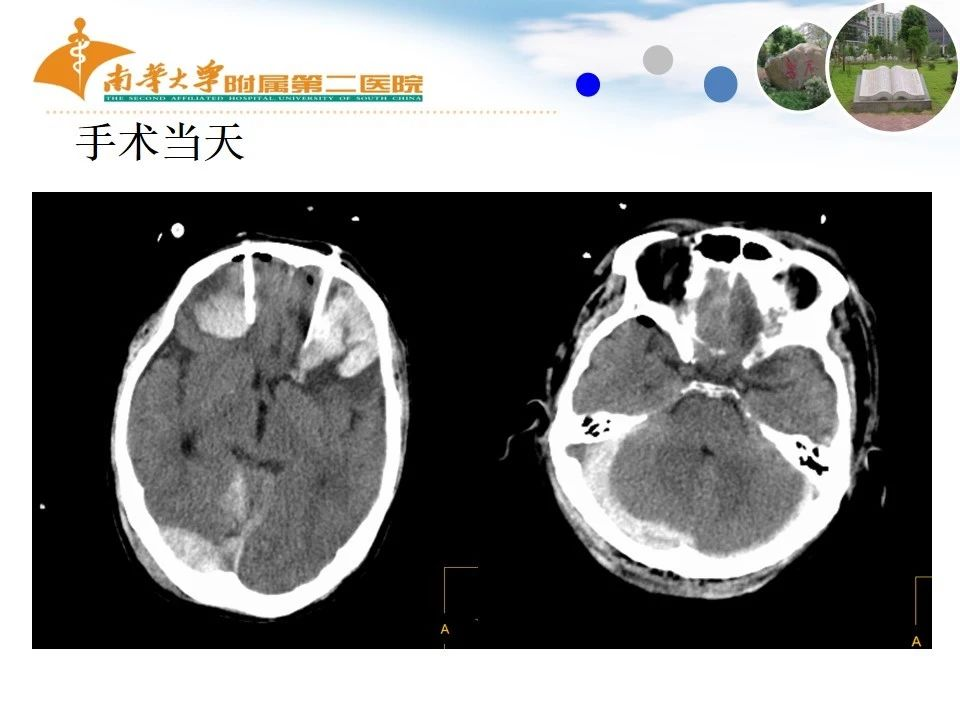

2. 手术指征及手术时机问题:患者昏迷、血肿量大于30ml。入院手术指征明确,但患者存在凝血功能障碍,尚未发生脑疝,可以先给予保守治疗,等待纠正凝血功能障碍后再手术。一旦病情加重发生脑疝,虽然未及纠正凝血功能障碍,也必须及时手术,一边输注血小板、新鲜冰冻血浆等纠正凝血功能障碍一边手术。如果术中发现确实止血困难无法清除脑内血肿,可以采取损伤控制外科技术,先行去大骨瓣减压缓解颅内高压,等待纠正凝血功能障碍后再进行确定性手术即清除脑内血肿。幸好患者未发生脑疝,可以等到凝血功能基本正常才手术,但期间用时3天,风险比较大,要引起重视。

3. 手术方式问题:该患者为颅内多发血肿,未提供全部层面的CT照片,但从受伤3天复查的CT发现双额叶血肿增加,占位效应主要为双额叶别是左额叶损伤为主,应该考虑首先清除双额叶血肿。枕部跨横窦的血肿没有增加且量不多,可以保守观察,或者是先做CTV或MRV,没有发现横窦受压闭塞无须手术。因此该例患者应该行冠状切口开颅双额叶血肿清除,或者是术中清除左额叶损伤后,监测颅内压不高,右额叶损伤也可以先保守。一旦术中发现明显颅内高压脑膨出还需去骨瓣减压。虽然该例经双额锥颅引流血肿最终治愈,但应该采取规范化的开颅手术,现有的治疗指南不提倡这种手术方式。锥颅血肿引流只能作为在不具备开颅手术条件且发生脑疝非常紧急情况下的一种临时急救措施。